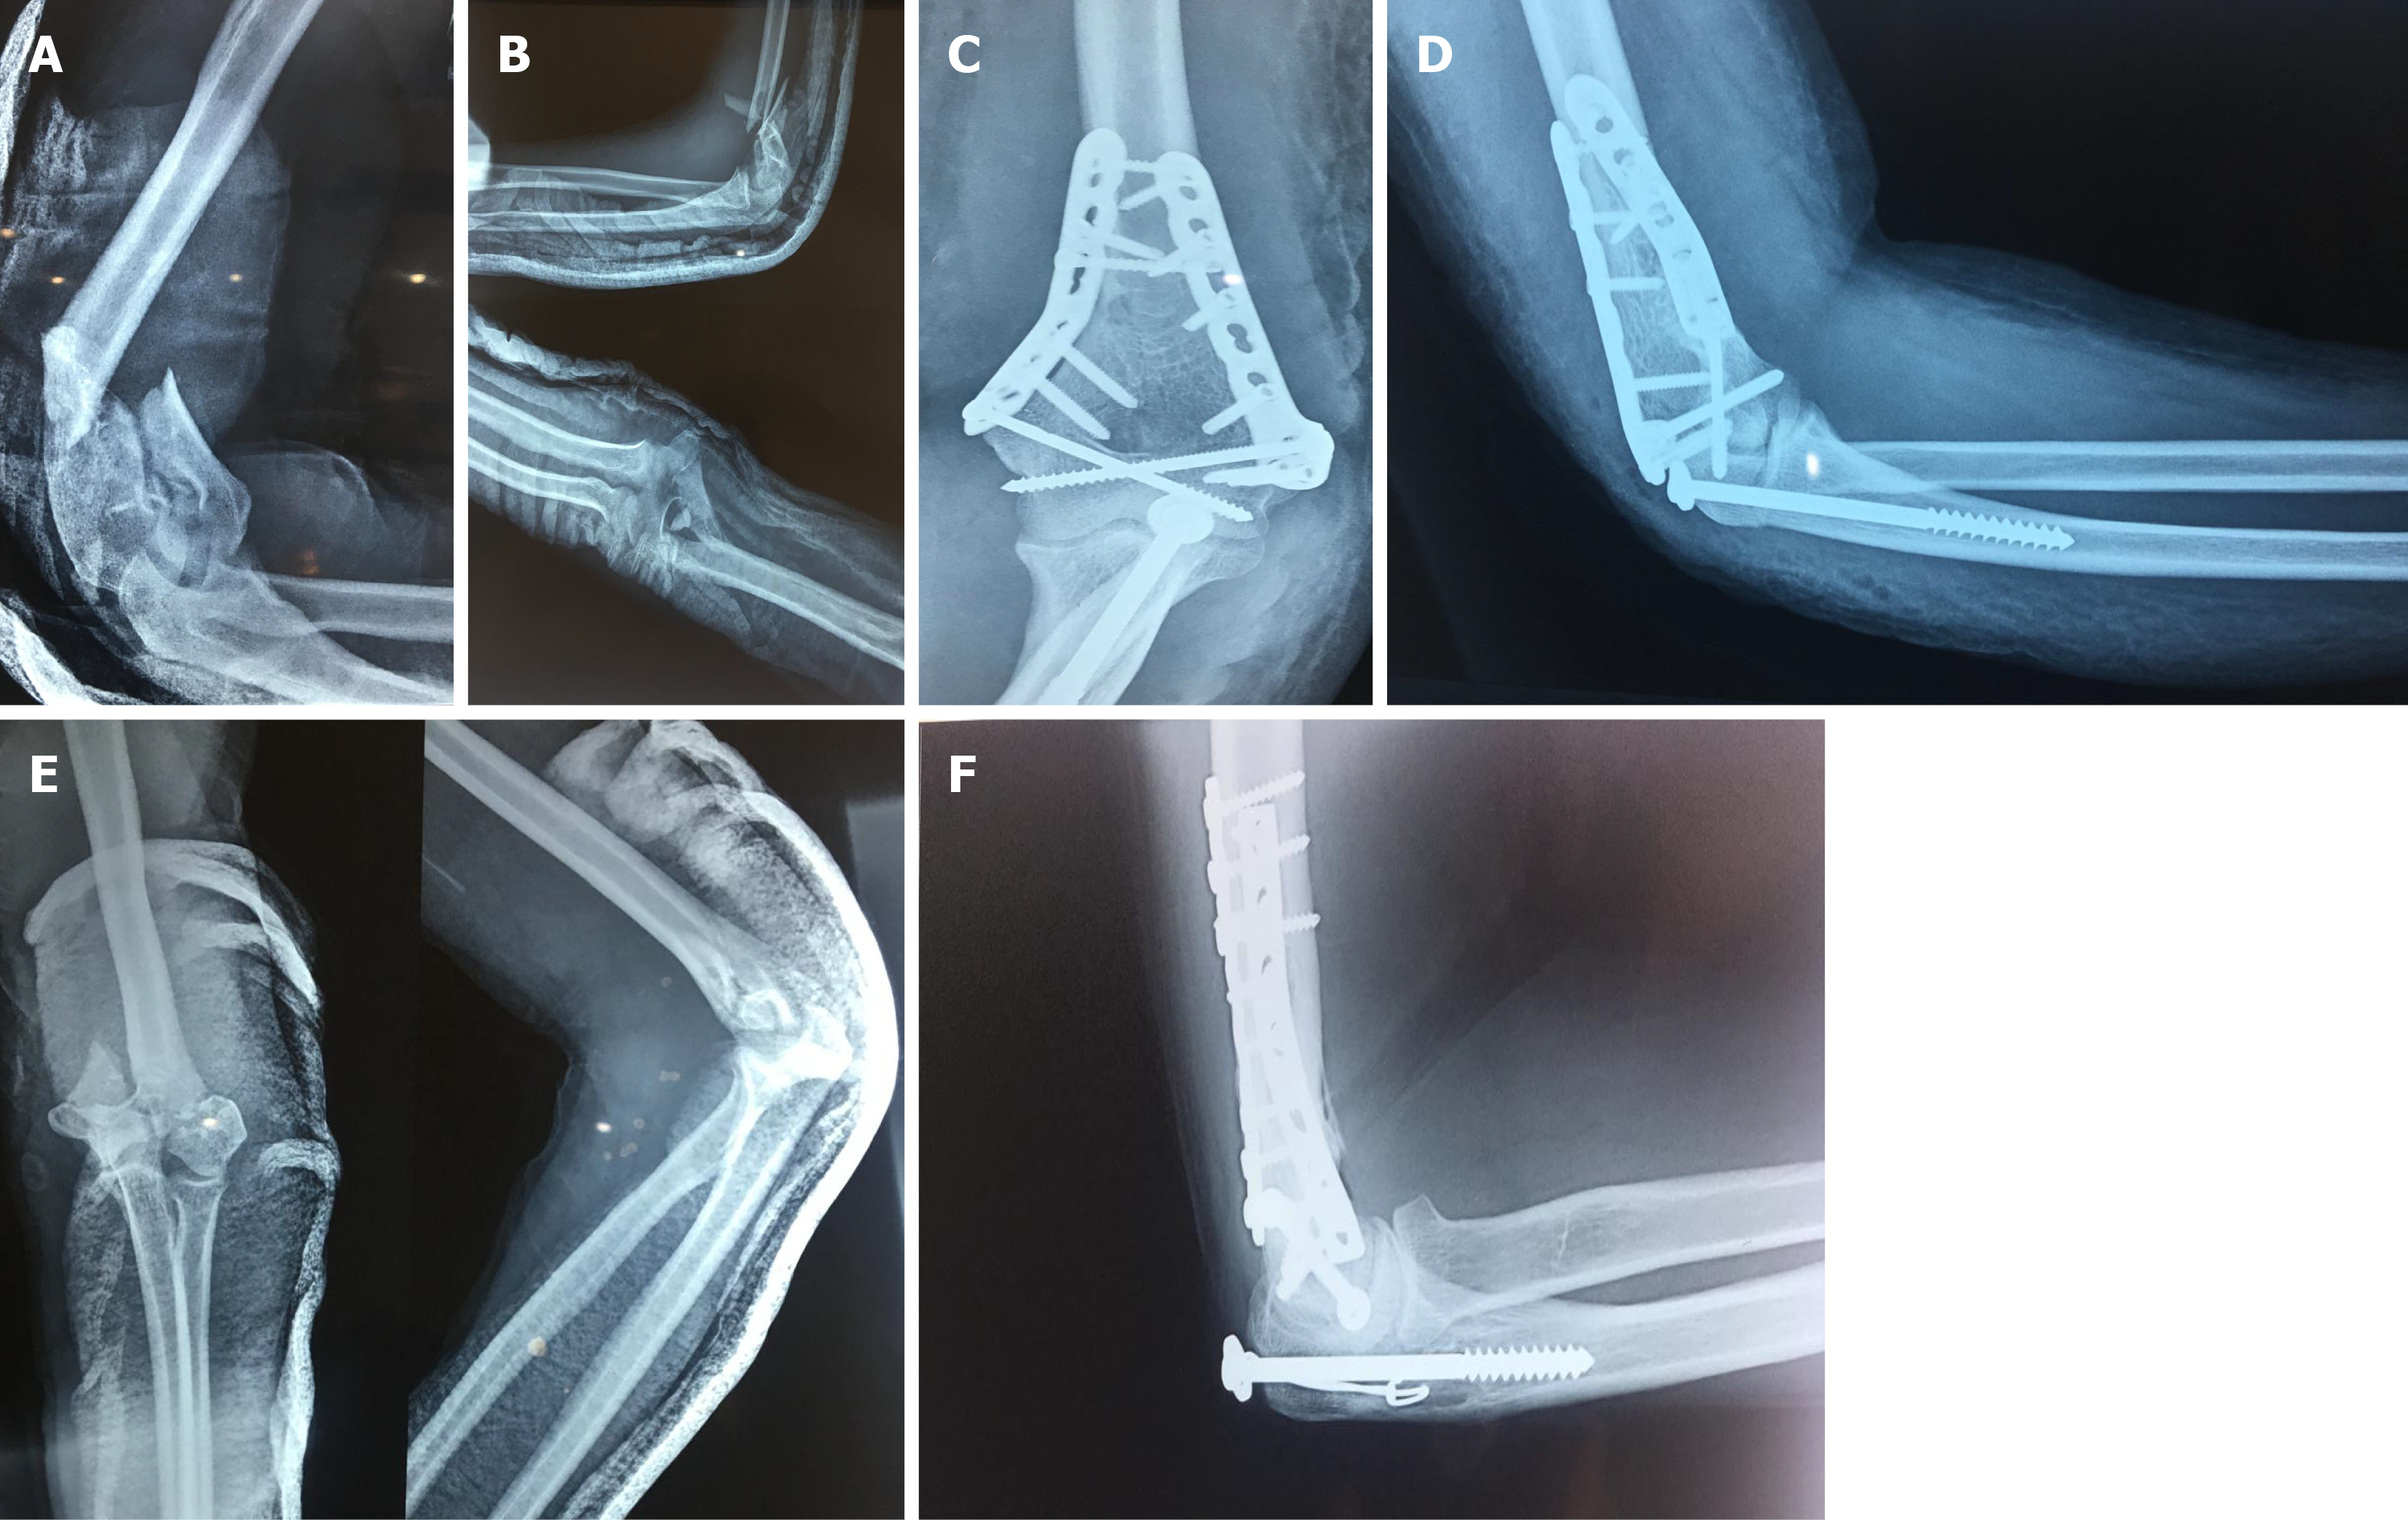

Standard identical protocol was adopted for olecranon osteotomy and fixation of intra-articular distal humerus fractures. All the surgeries were performed under general anaesthesia and pneumatic tourniquet control. All the surgeries were performed by the same surgical team (all three authors). All the operating surgeons were experienced trauma surgeons with more than ten years of treating complex elbow fractures. The patient was placed lateral decubitus position with the affected arm in arm holder. Preoperative intravenous antibiotics (injection cefuroxime) was administered at induction before tourniquet inflation. A straight incision on the posterior midline of elbow was given about 5 cm below the tip of olecranon and 5 cm above the olecranon. After soft tissue dissection ulnar nerve was identified and protected to one side with a sling. The site of olecranon osteotomy was marked with cautery about 2-2.5 cm distal to the tip of olecranon. A 2.8 mm guide wire was inserted intramedullary from tip of olecranon distally into the ulna and checked under image intensifier in AP and lateral views. A drill bit of 4.8 mm was inserted over guide wire till it touched the cortex of ulna. An appropriate size 6.5 mm partially threaded cancellous screw with washer was inserted into the medullary canal of ulna. Once ensured that the screw had a strong grip in diaphysis of ulna it is retracted back and engaged with tip of olecranon leaving only few threads inside the tip of olecranon. We performed transverse olecranon osteotomy with an oscillating power saw and completed with a chisel. The olecranon osteotomy along with triceps tendon was elevated to expose the intra-articular distal humerus fracture. The intra-articular distal humerus fracture is fixed with two locking compression plates on lateral and medial column and inter fragmentary screws when needed (Figures 1 and 2). The proximal olecranon osteotomy piece was placed on its original position and reduced with reduction a clamp. The cancellous screw was advanced intramedullary and tightened to achieve compression. The osteotomy reduction and screw positioning was confirmed in image intensifier.

Figure 1

Figure 1 Preoperative and postoperative X-ray films of distal humerus fractures and images of olecranon osteotomy fixation. A and B: Preoperative anteroposterior (A) and lateral radiographs (B) showing intra-articular distal humerus fracture; C and D: Postoperative anteroposterior (C) and lateral radiographs (D) showing healed fracture distal humerus and healed olecranon osteotomy fixed with cancellous screw and washer; E and F: Preoperative and postoperative radiographs showing fixation of olecranon osteotomy with intramedullary screw and cerclage. Preoperative anteroposterior and lateral radiographs showing intra-articular distal humerus fracture (E). Fixation with pre-contoured locking plates and olecranon osteotomy fixation with intramedullary screw and cerclage (F).

In patients with intramedullary screw and TBW construct two horizontal superficial holes in both cortices diaphysis of ulna was made with 3.2 drill bit about 4 cm distal to the osteotomy. An 18 gauge stainless steel cerclage is passed through these holes. The cerclage was applied around the tip of cancellous screw with washer in figure of eight as TBW. It is tightened firmly and screw is inserted over it (Figure 1E and F). The wound was closed in layers. An above elbow back slab was given for two weeks. At two weeks stitches were removed and slab discontinued. Identical supervised physical rehabilitation program was initiated which included initial range of motion exercises followed by gradual transition to active and passive elbow motion. Follow up visits were scheduled at four weeks initially for six months and then every third months thereafter.